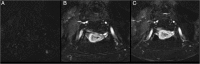

Endometrial cancer is the most common gynaecologic malignancy in developed countries and its incidence is increasing. First-level treatment, if no contraindicated, is based on surgery. Pre-operative imaging is needed for evaluation of local extent and detection of distant metastases in order to guide treatment planning. Radiological evaluation, based on transvaginal ultrasound, MR and CT, can make the difference in disease management, paying special attention to assessment of entity of myometrial invasion, cervical stromal extension, and assessment of lymph nodal involvement and distant metastases.